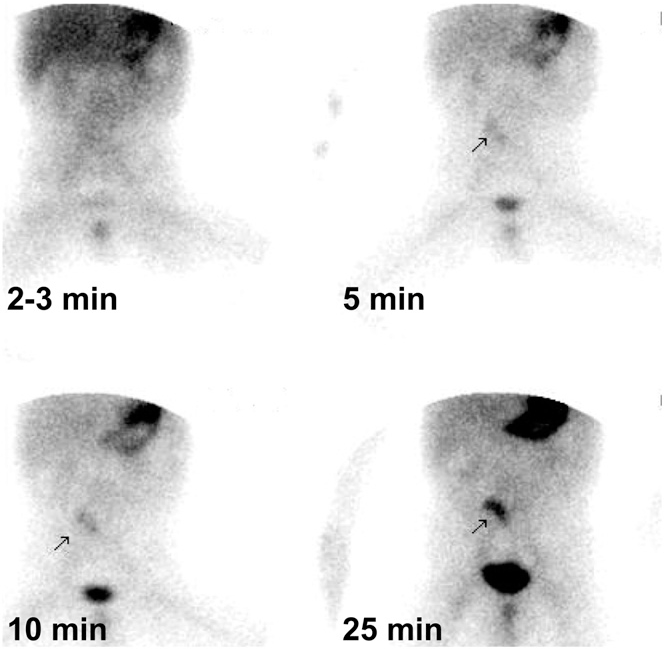

Radionuclide Scintigraphy

Advantages/ disadvantages

Radionuclide scintigraphy

(blurred picture of the skeleton; shady areas where the bleed is on)

Advantages:

- sensitive to lowe rates of bleed

- no bowel prep needed

- easily repeated if needed

Disadvantage:

- it is slow

- may delay therapeutic intervention

- diagnosis must be confirmed with endoscopy/surgery